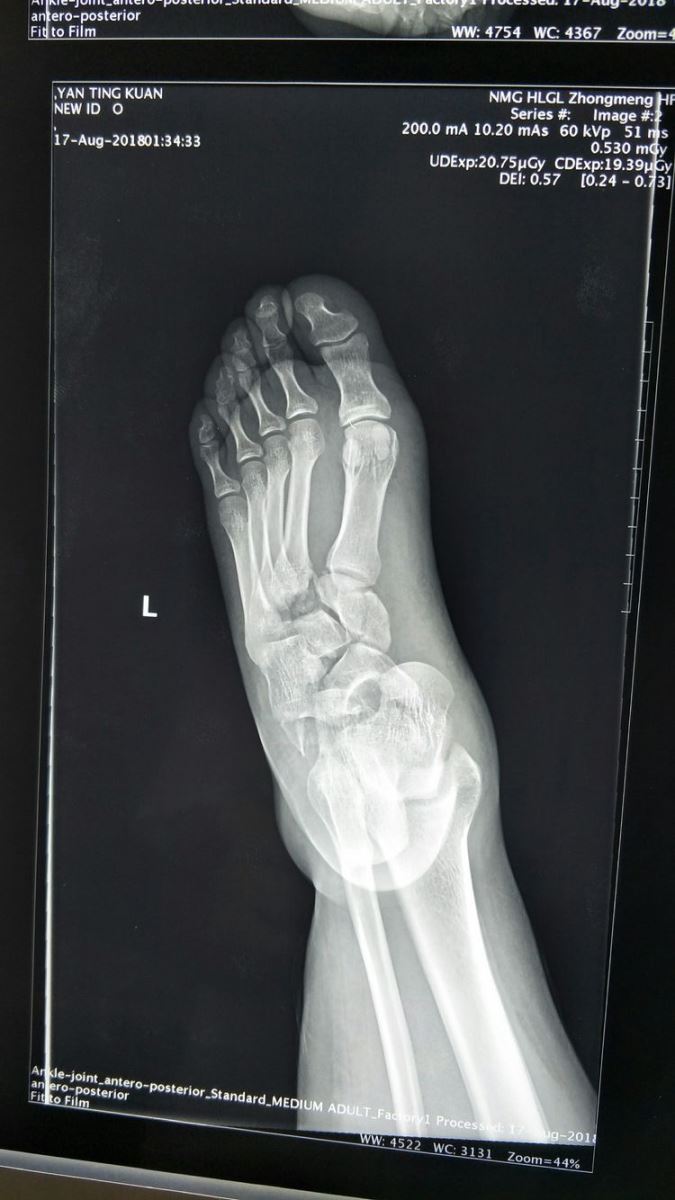

左足正位片:Chaopart关节脱位,内侧楔骨骨折,中间楔骨、外侧楔骨与骰骨之间关系紊乱,第一、二跖骨间距增宽,跖跗关节脱位。